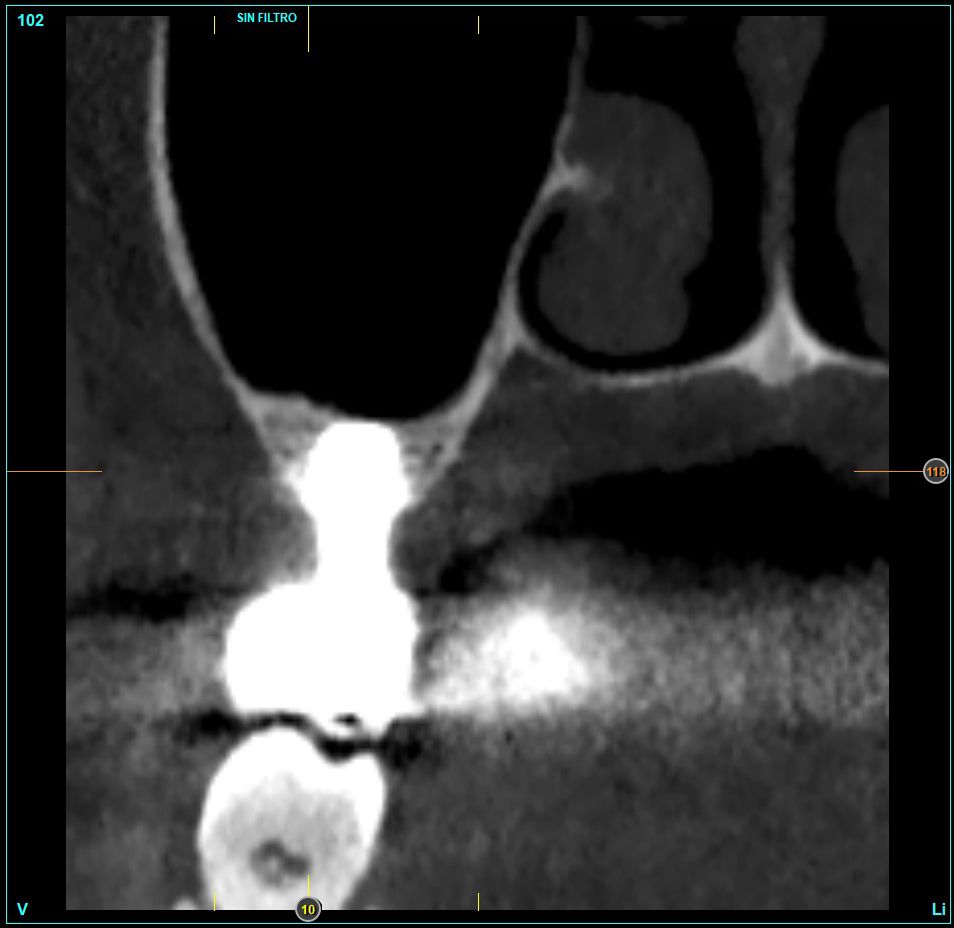

In all cases, a diagnosis was made based on study models, intraoral examination of the patient and performing a Cone-beam analysed using the specific BTI-Scan 3 software (Biotechnology Institute, Vitoria, Alava, Spain).

Patients attend subsequent check-ups performing a control Cone-Beam after 5 months (before loading the implant) and after one year of the load, performing a new measurement in these images to analyse the bone gain and the maintenance of the same. In these check-ups, data are collected on prosthetic complications or crestal bone loss in these patients, as well as possible failures.

The mean height of the residual bone volume was 3.1 mm (+/- 0.3 mm with a range of 3-4 mm). In all cases, transcrestal sinus elevation was performed, with particulate autologous bone obtained from milling the neo alveolus generation zone for implant insertion, being the average of this elevation above the apex of the implant of 2.8 mm (+/- 0.99 range 1.9 -5 mm). In the CT control scan after one year of inserting the studied implants, the bone gain achieved was maintained, no decrease in the volume gained was observed, only three cases showed a decrease of between 0.4 and 0.5 mm of the initial volume at the end (Table).

Figures 2-19 show one of the cases included in the study.